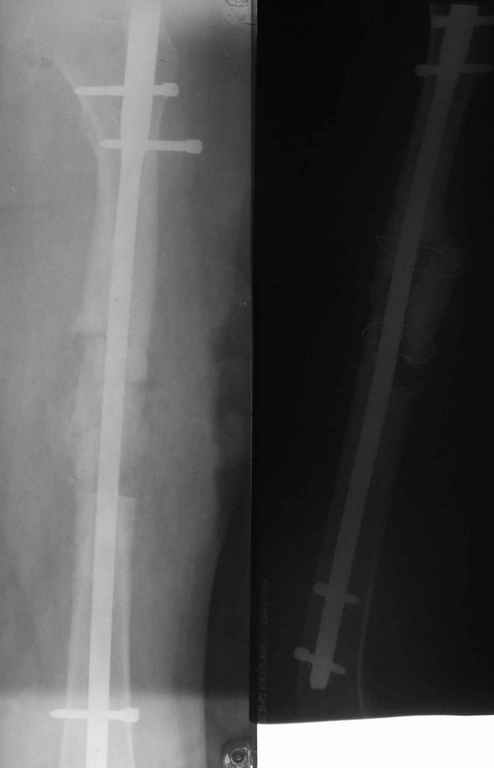

В нашей работе мы столкнулись с похожей ситуацией. У девушки 16-ти лет произошел изгиб интрамедуллярного штифта с вторичным смещением отломков бедра (гвоздь оказался тонковат, использовали, видимо, по принципу, что было под рукой). Вот только укорочение последнего составило 4см. Оперировали с обнажением места перелома, удлинили бедро на штифте ChM с элементами костной аутоплатики а-ля Хахутов. К слову, это был один из первых опытов использования нами БИОС вообще. Исходный результат - полная косолидация и выигрыш 3см, что расцениваем его как достойный данного изложения.